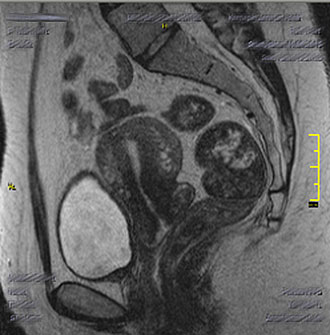

Bei Frauen liefert die MRT des Beckens wertvolle Informationen über die Harnblase, Gebärmutter, Eierstöcke und den Enddarm.

Die Untersuchung ermöglicht eine exakte Darstellung der Beckenorgane und hilft, gutartige von bösartigen Veränderungen zu unterscheiden – wichtig für eine gezielte Therapieplanung.